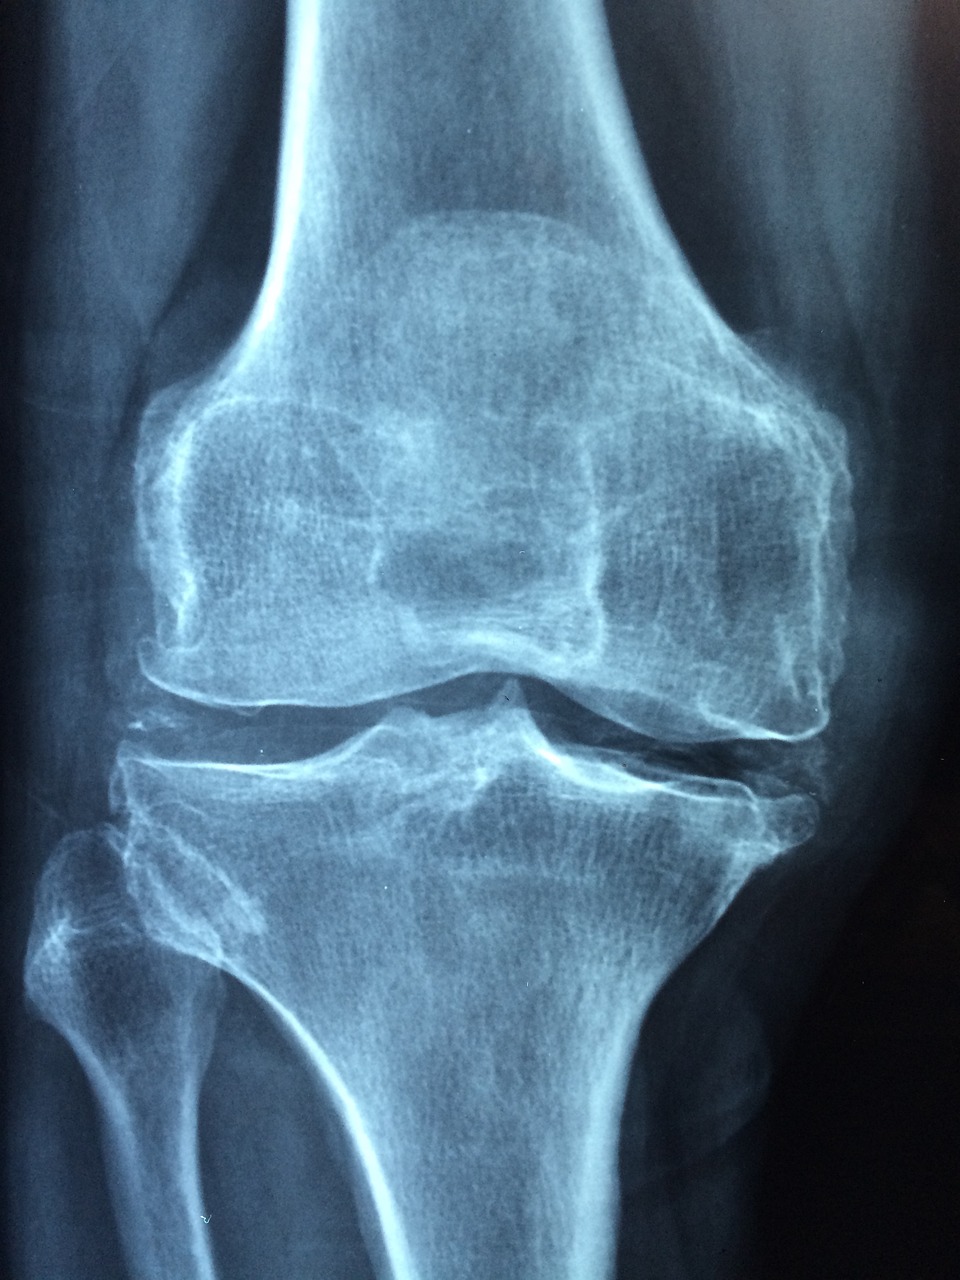

골다공증은 뼈의 밀도가 낮아지고 구조가 약해지면서 쉽게 골절이 발생하는 질환으로, 특히 중년 여성에게 매우 흔하게 발생합니다. 폐경 이후 여성호르몬 감소로 인해 뼈 손실이 가속화되며, 특별한 외상 없이도 척추나 대퇴골 골절이 일어날 수 있습니다. 이번 글에서는 골다공증이 왜 중년 여성에게 흔한지, 어떤 생활 습관으로 예방할 수 있는지, 뼈 건강을 지키기 위한 실천 방법들은 어떤 것이 있는지 단계별로 소개해 드립니다.

골다공증은 특히 폐경기 이후 여성에게 집중적으로 발생합니다. 이는 여성호르몬인 에스트로겐이 뼈를 보호하는 역할을 하는데, 폐경 이후 에스트로겐 수치가 급격히 떨어지면서 뼈의 재흡수가 촉진되고, 뼈 생성 속도는 감소하기 때문입니다. 결과적으로 뼈의 밀도가 줄고 약해지면서 골절 위험이 커지게 됩니다. 실제로 50세 이상 여성의 절반 이상이 골다공증 또는 골감소증을 앓고 있으며, 특히 척추압박골절, 대퇴골 골절 등의 문제는 삶의 질을 심각하게 저하시킬 수 있습니다. 문제는 골다공증이 초기에는 자각증상이 거의 없다는 것입니다. 뼈가 점점 약해지지만 통증이 없어 방치되기 쉽고, 골절 후에야 골다공증을 진단받는 경우가 많습니다. 또한 중년 여성은 갱년기를 겪으면서 운동량이 줄고, 우울감이나 수면 장애로 인해 활동성이 떨어지는 경우가 많습니다. 이러한 변화는 체내 칼슘 흡수를 저하시킬 뿐만 아니라, 뼈를 자극하는 기계적 자극도 줄어들게 하여 골밀도 저하로 이어집니다. 따라서 중년 여성이라면 폐경 전후로 정기적인 골밀도 검사를 받고, 골다공증의 위험을 조기에 인식하는 것이 중요합니다.